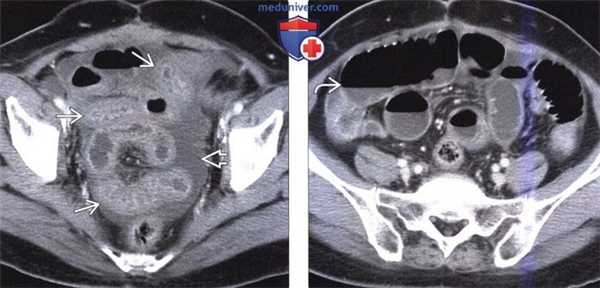

(Слева) На аксиальной КТ без контрастного усиления определяется распространенная инфильтрация брыжейки трансплантата тонкой кишки наряду с утолщением стенки кишки. Эти изменения являются частыми неспецифическими находками у реципиентов трансплантата тонкой кишки.

(Справа) На аксиальной КТ без контрастного усиления определяются уровни «жидкость-жир», свидетельствующие об ограниченном хилезном асците с наличием жидкости между петлями трансплантата тонкой кишки. Утечка жидкости из лимфатических капилляров обычно разрешается с течением времени по мере восстановления их целостности, однако в некоторых случаях может потребоваться чрескожное дренирование с целью удаления жидкости.

(Слева) На КТ без контрастного усиления определяется дилатация аллотрансплантата, а также утолщение его стенки и пневматоз, что является крайне подозрительным признаком инфаркта трансплантата.

(Справа) На КТ без контраста у этого же пациента определяется пневматоз ближайших отделов трансплантата тонкой кишки. При эндоскопическом вмешательстве (через илеостому) не было обнаружено изменений внешнего вида слизистой оболочки. Пневматоз стенки трансплантата тонкой кишки встречается нередко и может быть результатом инфаркта, приема лекарственных препаратов, применяемых для профилактики отторжения, обструкции кишечника или иных «доброкачественных» причин.